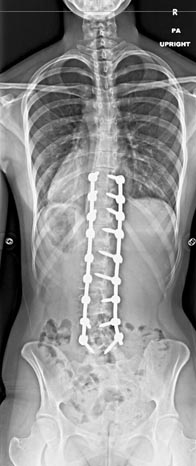

67 year old woman with Parkininsons presenting with neuromuscular kyphoscoliosis with inability to stand and look upright. Patient expressed that she was tired of talking to other people’s belly buttons.

T2 to sacrum/pelvis spinal fusion. Patient is pain free and able to stand upright and walk normally for the first time in years.